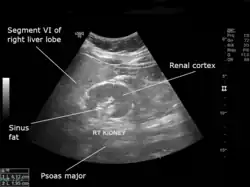

| An ultrasound scan of a hypoplastic right kidney in an adult male. | |